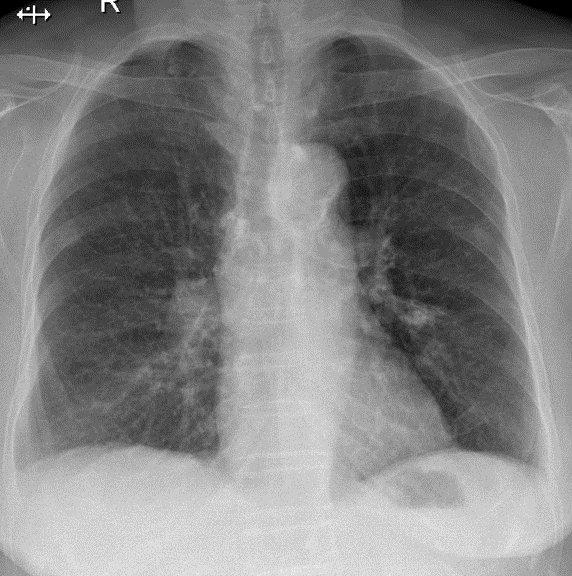

Hãy phân tích tình huống Nữ 82 tuổi

1-Đóng vôi sụn khí phế quản 2-Xơ vôi thùy dưới phổi (T) 3-Cung động mạch chủ đóng vôi